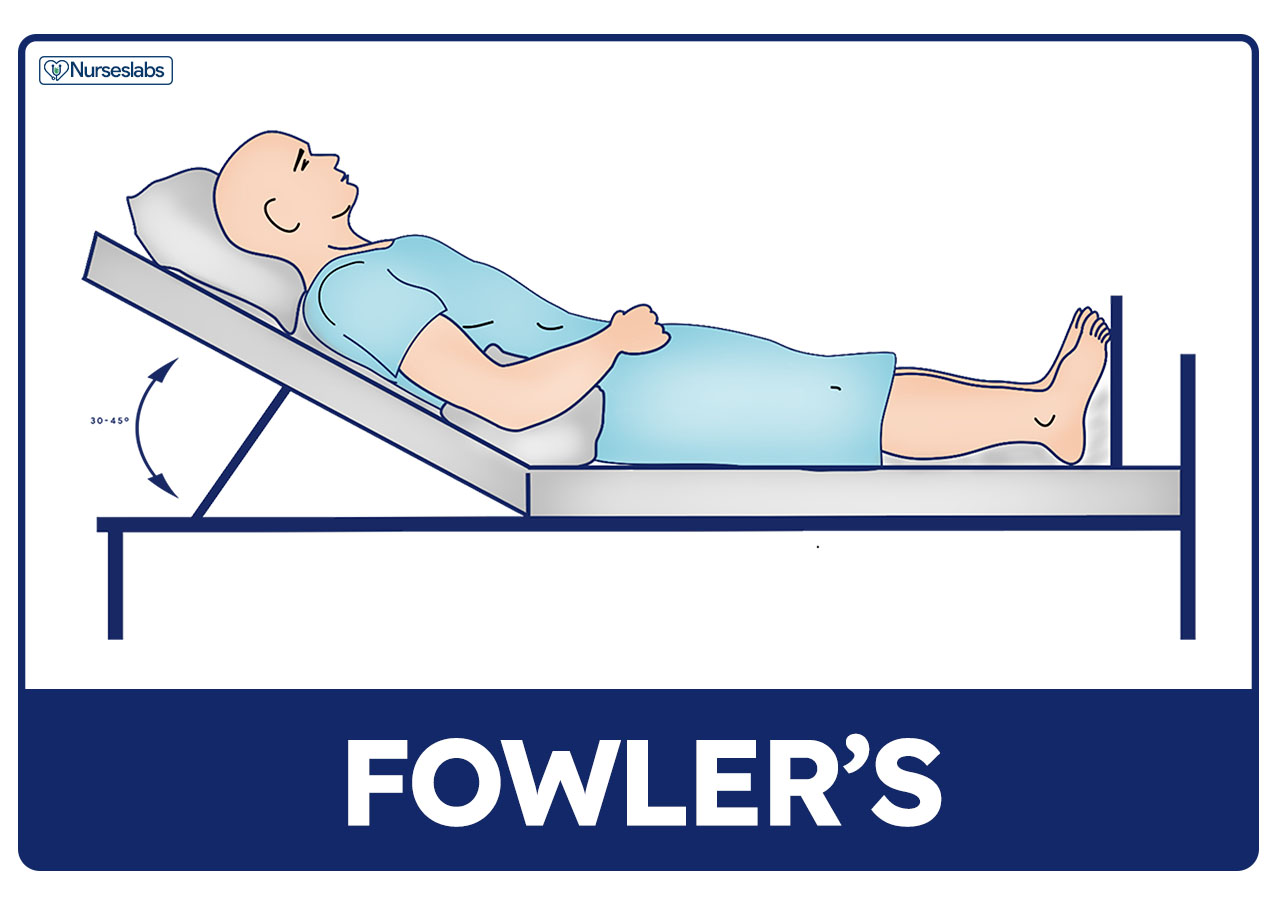

30 degrees

ensure head of bed is elevated to _______ to reduce risk of aspiration and GERD

*repositioning patients is key, closely watch ventilated/sedated patients on enteral (tube) feeding

FASTHUGSBID - Head of Bed